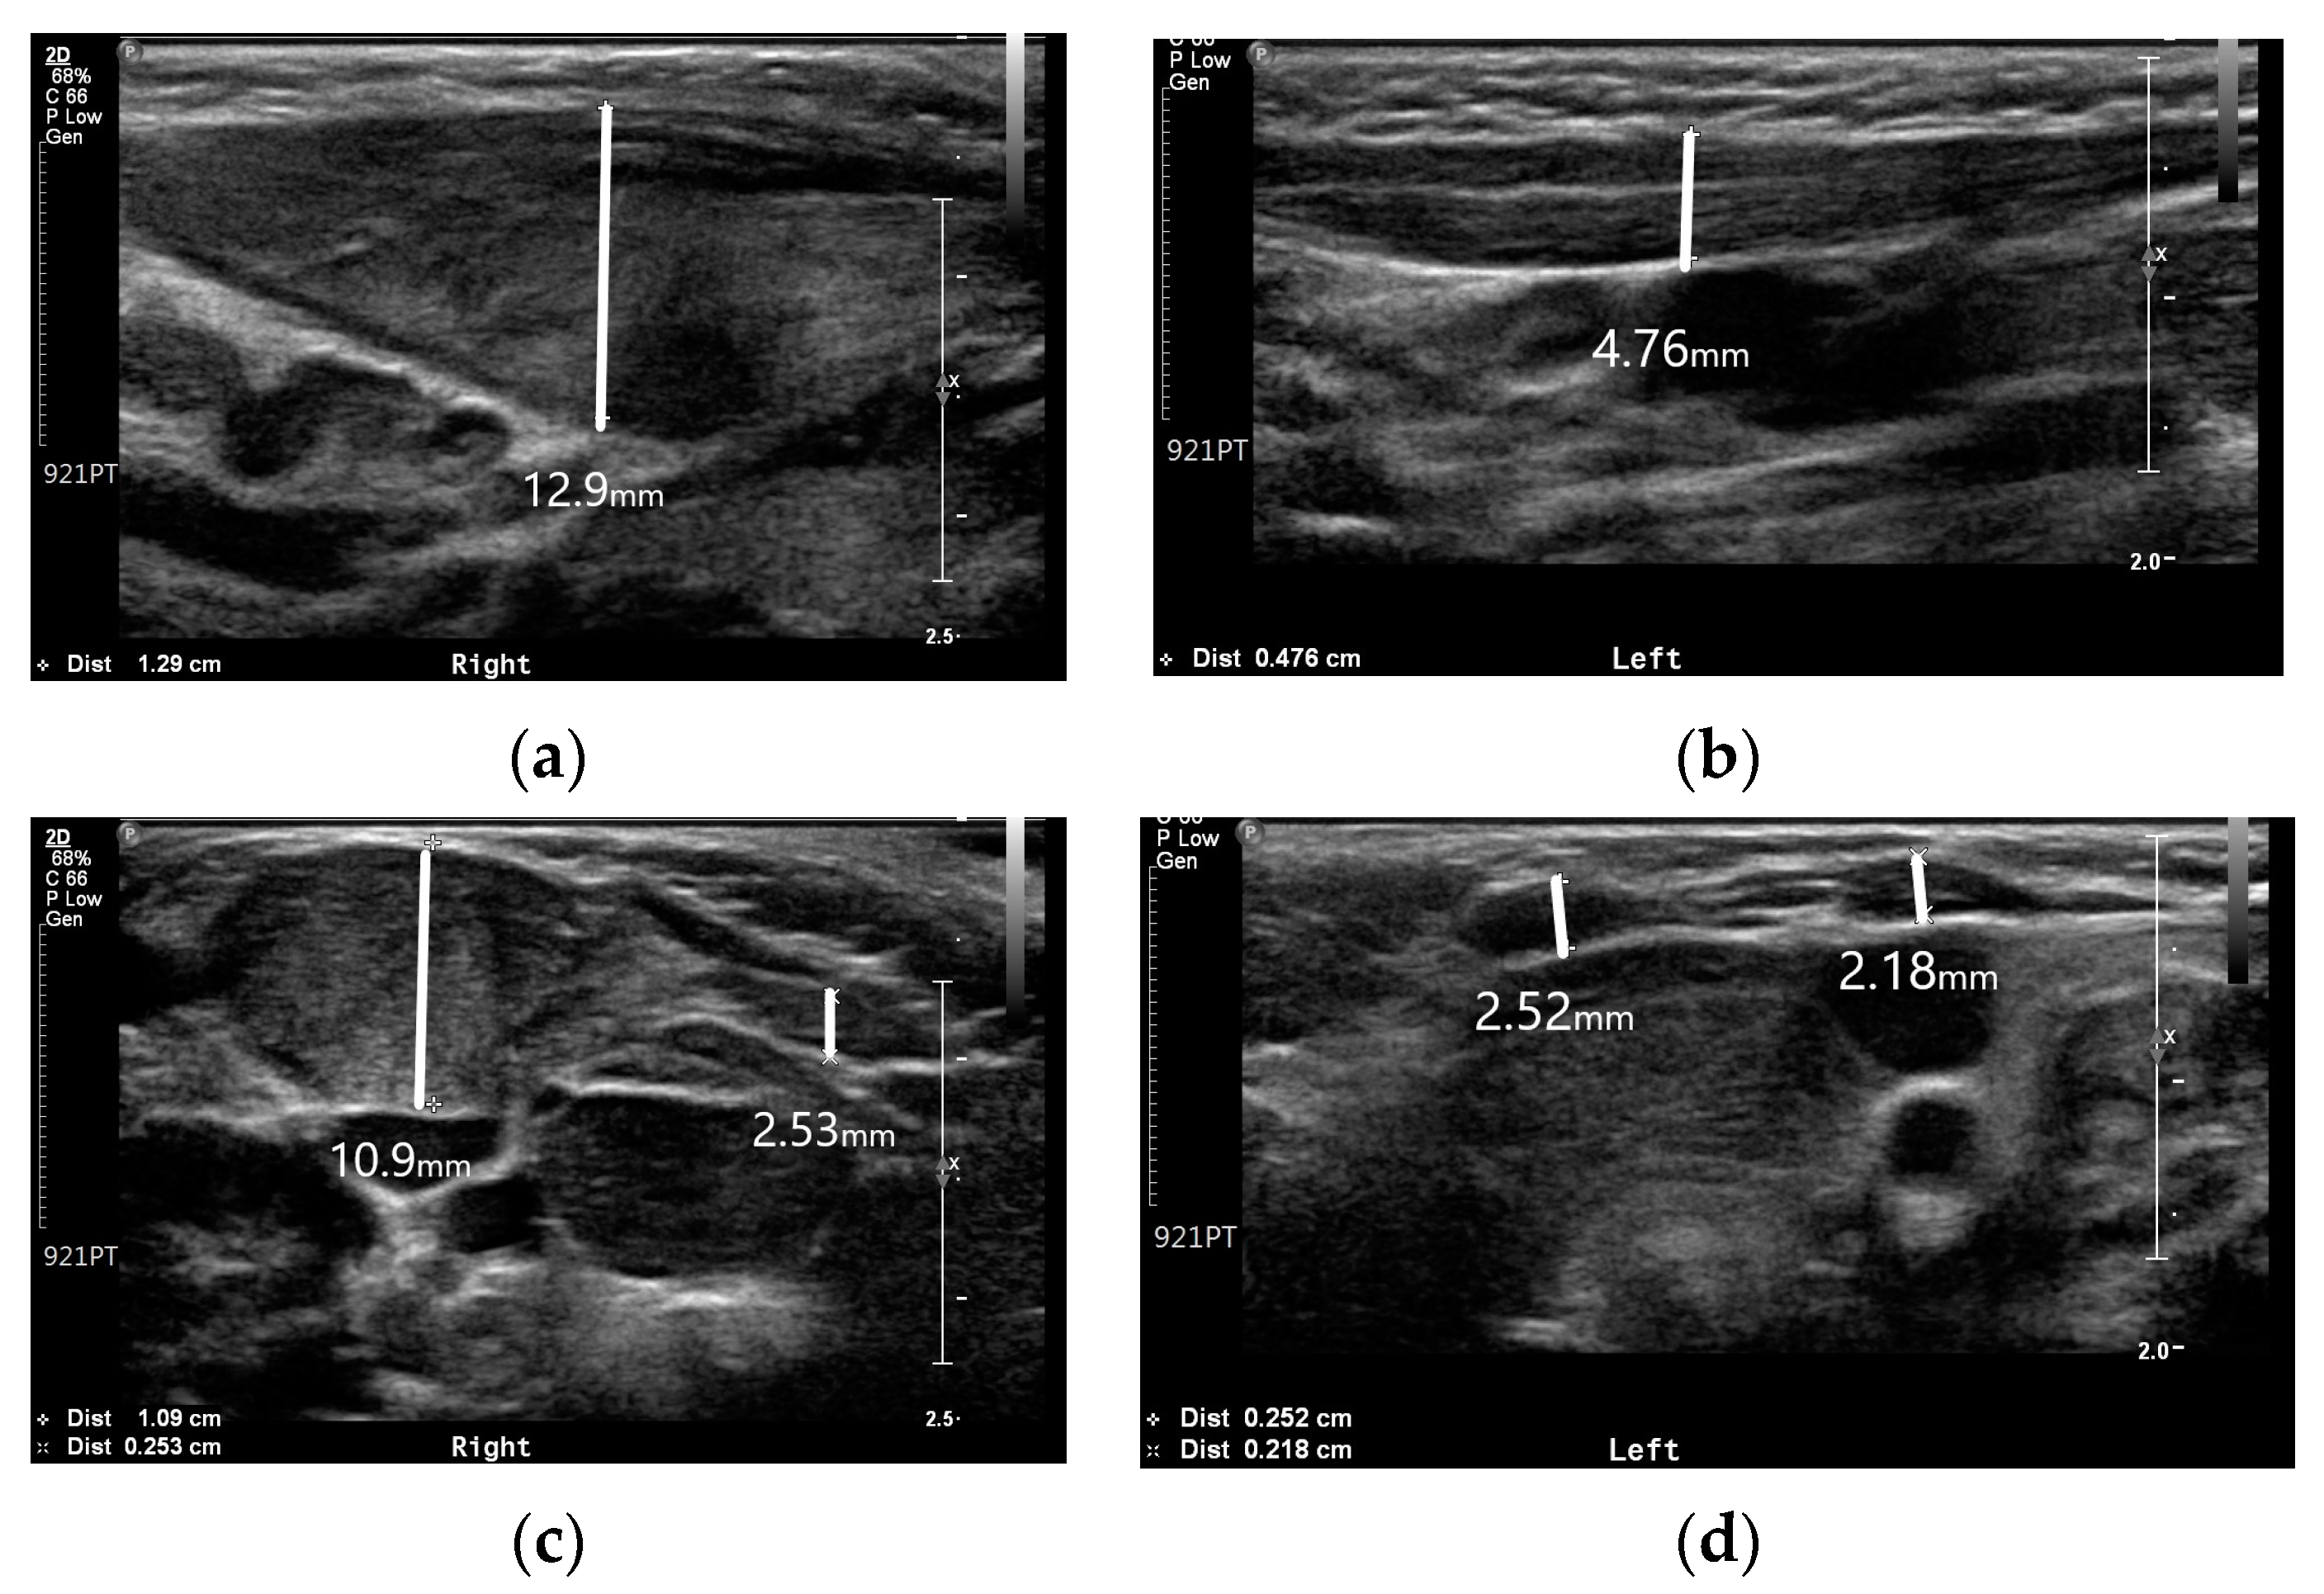

Ultrasound is the imaging modality of choice for radiographic evaluation of congenital muscular torticollis [8]. On ultrasound images, the SCM muscle appears as a relatively hypoechoic mass with echogenic lines; however, in cases of congenital muscular torticollis, the thickened SCM muscle mass can affect the size and signal intensity of the muscle. In conditions of congenital muscular torticollis, the affected SCM muscle looks thicker than the normal contralateral side, and the signal intensity of the muscle tends to be more hyperechogenic [8]. Neck ultrasonography exhibited asymmetric thickening of the right SCM muscle with hyperechogenicity (Figure 2). The thickness values of the SCM muscle at the right and left mid-levels were 12.9 and 4.7 mm, respectively, while the thickness values at the clavicular insertion point on the right and left sides were 10.9 and 2.1 mm. At the sternal insertion point, the right- and left-side thickness values were both 2.5 mm, and the baby exhibited prominent right-side muscular torticollis with fibromatosis coli.

Although idiopathic muscular torticollis was prominent, it can be viewed as a secondary change due to ipsilateral hemihypertrophy. According to a previous study by Hwang et al. [11], the average thickest part of the unaffected SCM muscle was 5.9 ± 1.1 mm, no more than 20% greater than that of the unaffected side. In this patient, the thickness values of the unaffected and affected sides were 4.7 and 12.9 mm, respectively. This discrepancy suggests that the SCM muscle was affected by ipsilateral hemihypertrophy.

Figure 2. Neck ultrasonography of the SCM muscle: (a) Thickness of the right SCM muscle at mid-level; (b) Thickness of the left SCM muscle at mid-level; (c) Thickness of both SCM muscles at the clavicular insertion site; (d) Thickness of both SCM muscles at the sternal insertion site.